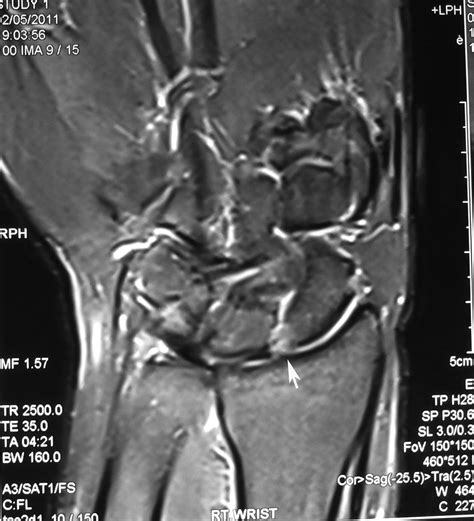

Diagnosing a Ligament Tear of the Wrist

Diagnosing a ligament tear of the wrist typically involves a combination of physical examination and imaging tests. A healthcare provider will:

• Order imaging tests, such as X-rays, MRI, or CT scans, to visualize the extent of the injury.